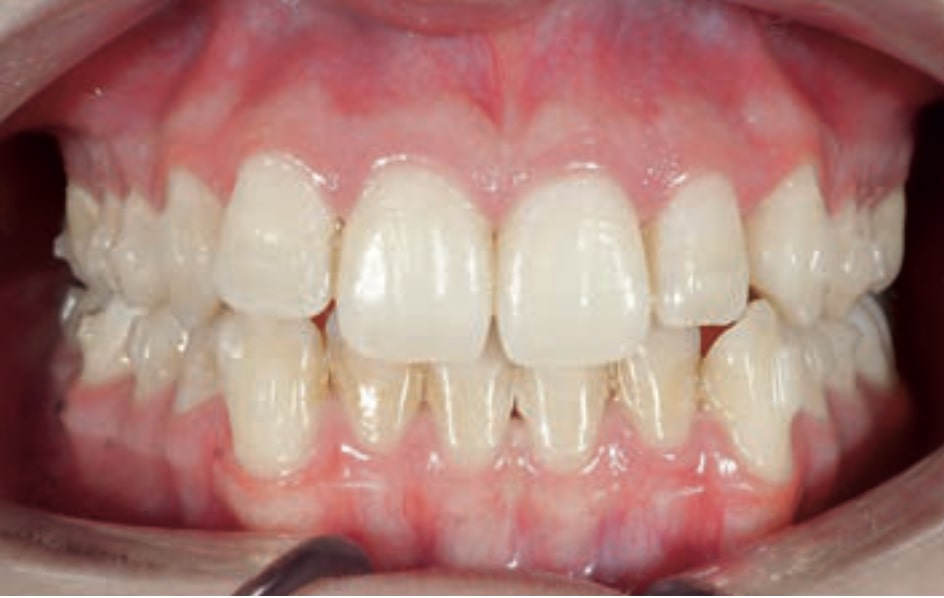

Chief complaint: The patient, a 19-year-old woman, was evaluated to undergo orthodontic treatment using the Angel Aligner Pro system. She presents with a skeletal Class III, mesofacial, with a dental Class III malocclusion and a 2 mm deviation of the lower midline to the left. Teeth 33 and 43 are out of the arch and cortical bone, with a crossbite issue on tooth 33. Fortunately, no functional issues affecting swallowing or breathing have been detected. The patient’s motivation for starting treatment was a general review of her dental and aesthetic health. The soft tissue analysis reveals mandibular protrusion that influences her facial profile. This diagnosis highlights the need for a comprehensive approach to address dental and skeletal misalignments, improving both the patient’s functionality and facial aesthetics.

- Dental Class III, 2 mm deviation of the lower midline to the left. 33 and 43 out of the arch and the cortical bone.

- Crossbite of 33.